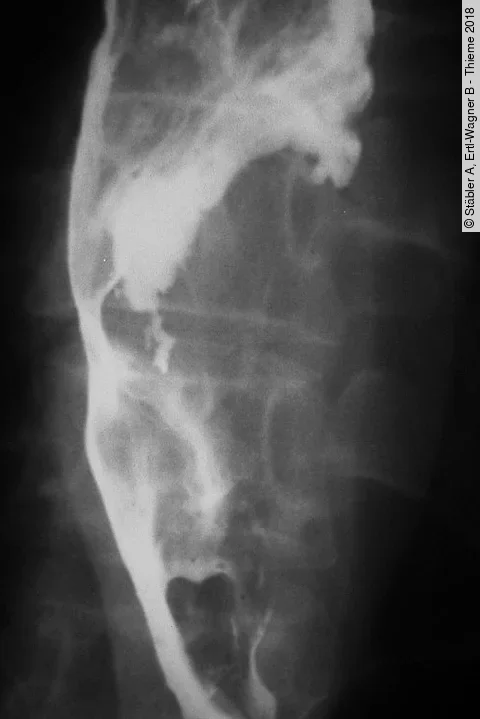

QuizAuflösung: 68-Jähriger mit Schluckbeschwerden

Der Patient hat ein Leiomyosarkom des Ösophagus.